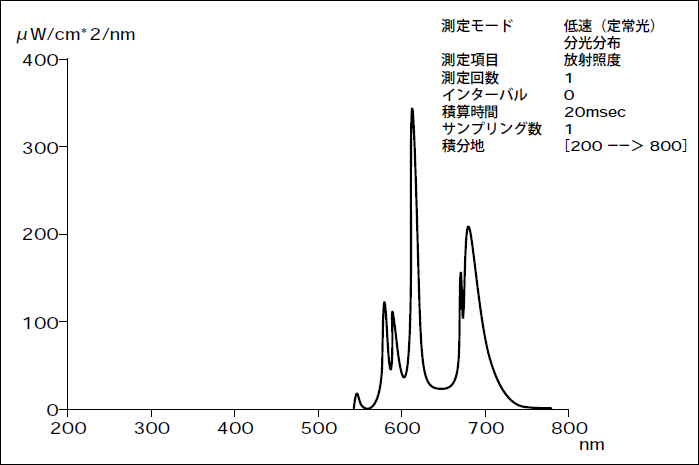

光線力学療法(PDT)は安全性の高い皮膚癌治療法のひとつとして期待されている。そこで今回は、簡便な臨床応用を目的に非レーザー光源(メタルハライドランプ)および光感作物質として20%5 -aminolevulinic acid(5-ALA)含有軟膏を用い、紫外線癌である日光角化症8 例に対してPDT を施行、有効性が認められるか否かを観察した。さらに、InvitroでPDT効果の機序にアポトーシスが関与するか否かを観察した。

20%5 - aminolevulinic acid(5-ALA)含有軟膏を密封塗布(6h)。ハロゲンランプ(500W)にて20分間(120J/cm2)照射した。